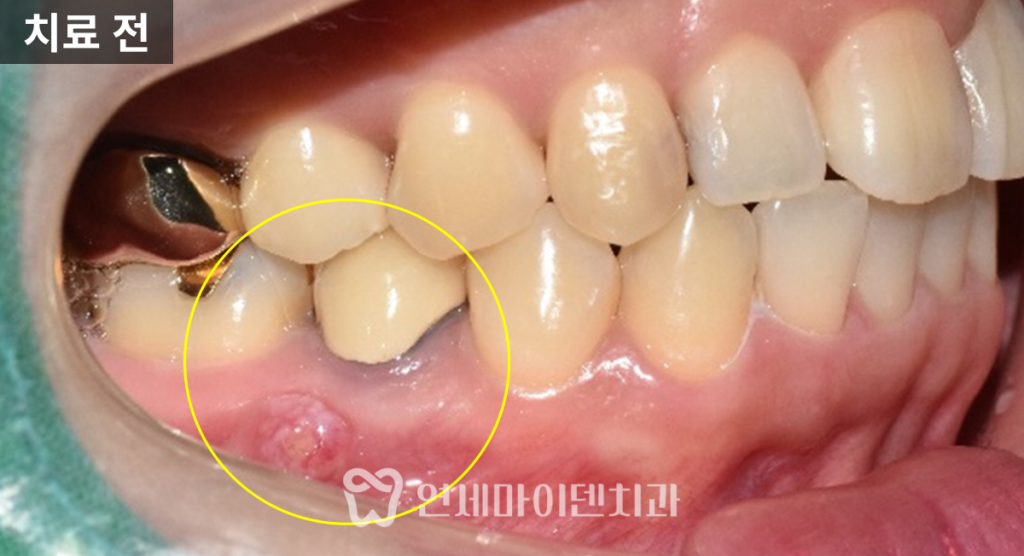

오늘 소개해드릴 사례는

과거 신경치료를 받았던 치아에서

잇몸 고름이 주기적으로 발생하던 케이스입니다.

통증은 심하지 않았지만

잇몸 색이 변했고,

고름이 올라왔다가 사라지기

오랫동안 반복하고 있었습니다.

장기간 방치하면서

잇몸뼈는 상당히 녹아 있었고,

반대편 치아는 이미 비슷한 문제로

발치한 상태였습니다.